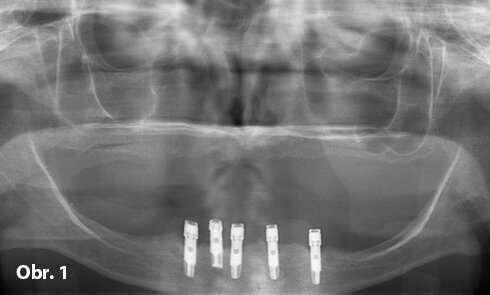

Předoperační snímek pěti stěsnaných implantátů ve frontálním úseku mandibuly